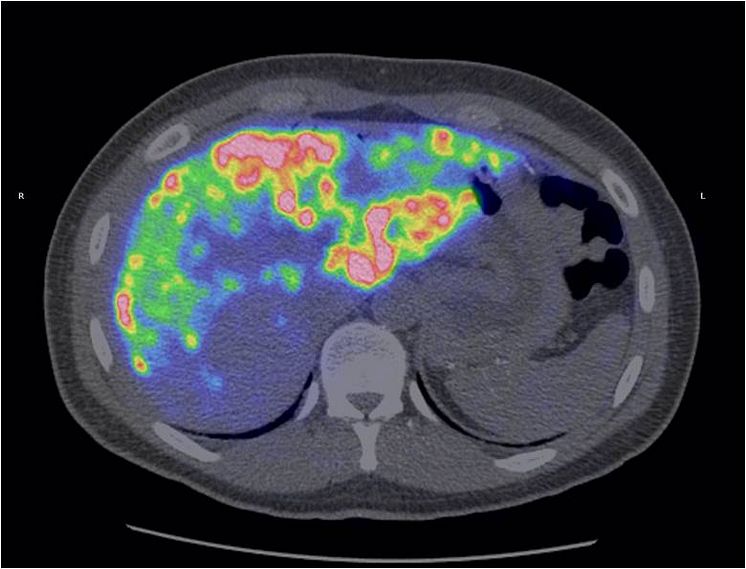

Med hjälp av den radioaktiva märkningen kan ö-cellerna följas i kroppen med hjälp av en s.k. PET-kamera.